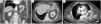

We report the case of an 80-year-old woman with a history of cholecystectomy who consulted for pain in the right iliac fossa. Examination revealed signs of peritonitis in the mesogastrium, and blood tests showed raised levels of acute phase reactants. Computed tomography was performed, showing segmental bowel wall thickening in the context of probable ileitis, a Bochdalek diaphragmatic hernia (BDH) containing the left kidney (Fig. 1A), and pleural effusion with underlying atelectasis of the left lower lobe (Fig. 1B and C).